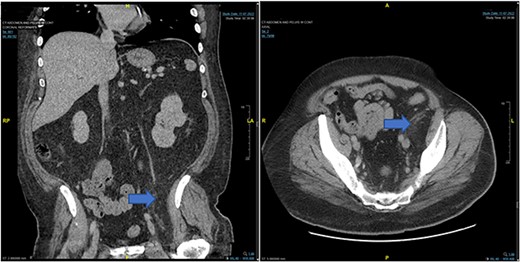

In the emergency department, vital signs were remarkable for elevated blood pressure of 166/81, but otherwise stable and afebrile. WBC count was elevated at 15.4 with left shift and hemoglobin was low at 9.6. Complete Metabolic Panel was notable for hyponatremia of 128, and mildly elevated BUN/serum creatinine of 26/1.5 which was slightly higher than his baseline of 17/1.3. Liver function tests were unremarkable. UA showed likely UTI with positive esterase, high RBC/WBC and bacteria and protein. A CT of the abdomen and pelvis was done, showing a left non-obstructing kidney stone and a left retroperitoneal fat density with stranding along the left iliopsoas measuring 12.6 × 8.1 cm × 3.7 cm, which was described as possibly a part of infectious or malignant process (Fig. 5). Subsequently, patient’s prior CT scans were available to be reviewed and it showed the same lipomatous mass 9 years earlier. (Fig. 6). Given the patient’s symptoms of left lower extremity pain and the possibility that the mass was responsible, a CT-guided core biopsy was ordered for diagnosis to rule out a malignant process as operative intervention was being contemplated. Pathology report of the core biopsy showed lobules of univacuolated adipocytes divided by thin septa. There were frequent multivacuolated adipocytes with small round nuclei, reminiscent of brown fat cells. No enlarged hyperchromatic cells, mitotic figures nor necrosis are seen. The findings supported the diagnosis of the lipoma variant of hibernoma (Fig. 4). Given the chronicity of the mass, the near identical size over 9 years and the diagnosis made from core biopsy, it was determined that the hibernoma was not the likely source of the patient’s LLE pain and hence the mass was not excised.